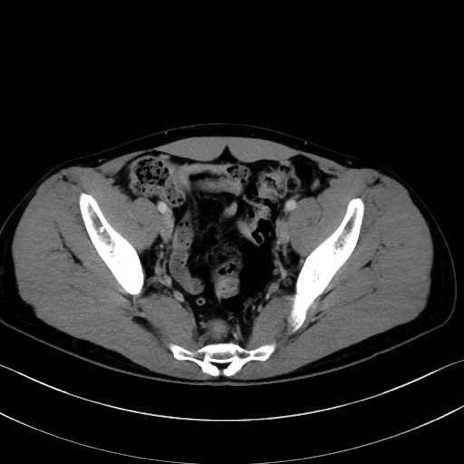

内閉鎖筋(obturator internus) のCT画像の解剖

内閉鎖筋 (Obturator internus)